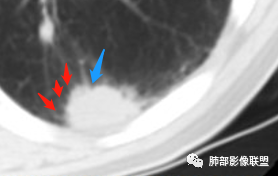

初学者:脐凹?

大部分病灶都是平直。一元就是肉芽肿性炎:隐球菌,类风湿结节。。二元就是这个脐凹,局部膨隆和坏死的家伙是二元肺癌。

南边:糊墙,长轴与胸膜平行;边缘收缩+膨隆;脐凹征

脐凹征,高度提示恶性

南边老师论述:    分叶凹陷的地方有血管,支气管进去,这个价值很大,后来引申到血管、支气管从凹陷的地方进去就叫脐凹征,就像番茄柄🍅,辣椒柄、苹果柄🍎一样的。后来就把这个做为脐凹征,95%以上的特异性。如下例:

后来发现胸膜牵拉,由远端凹陷的地方进去,他的价值也很大,诊断腺癌,几乎很少失误,后来把这个也纳入到脐凹征里。由凹陷处进入的胸膜牵拉征,由凹陷处进去的血管,都属于脐凹征。原理是由凹陷处进去的血管,因为肿瘤膨胀生长,生长过程中遇到血管,支气管区域受阻,边缘代偿性生长,膨胀的更厉害了,所以局部凹陷,前提是血管、支气管肯定在肺门侧,不会在远端有一条血管阻碍他的,可能性太小了。

脐凹征,支气管、血管引起的在肺门侧,因肿瘤生长在近端膨胀受阻的,病灶本身围绕支气管、血管周围包绕的不算,只有进去其中受阻的才算。